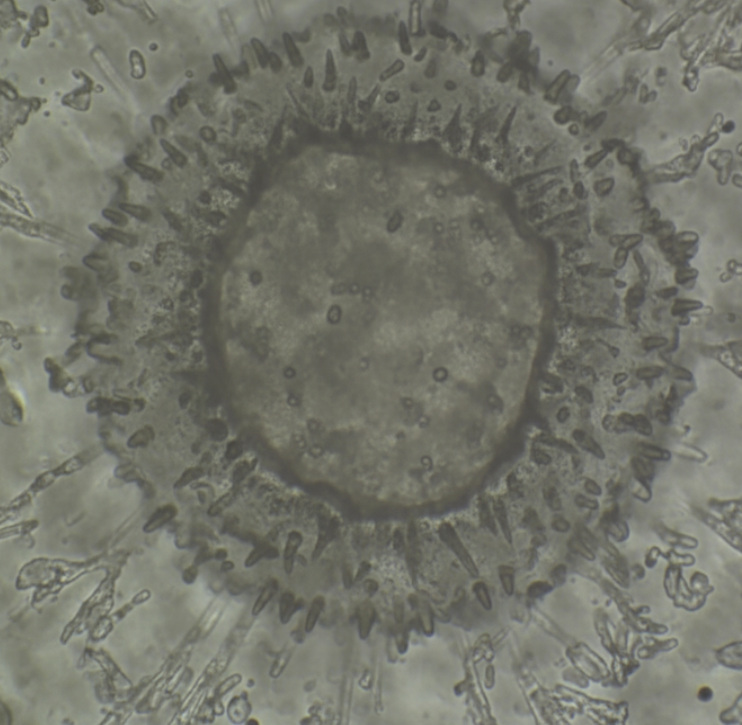

Um die Auswirkungen der extravasalen Laserblutbestrahlung mittels dem IPU7 Biophotonen LASER zu verdeutlichen, wurden Dunkelfeldmikroskop-Untersuchungen eines Tropfens Vitalblut vor und unmittelbar nach einer 30-minütigen Stimulation am Handgelenk durchgeführt.

Bei dem Probanden (Abb.oben - vor Anwendung) zeigte sich eine deutliche Agglutination („Geldrollen-Bildung“) der Erythrozyten (roten Blutkörperchen).

Dies ist ein Zeichen für Durchblutungsstörungen, bedingt durch Übersäuerung, Sauerstoffdefizite und Sauerstoff-Eisen-Transport-Probleme. „Geldrollen-Bildung“ bedeutet Verklebung oder auch Verklumpung der roten Blutzellen.

Dadurch wird die Aufnahme von Sauerstoff sowie von Eisen massiv eingeschränkt, da die Bindungsflächen für diese Moleküle durch die Verklebung verdeckt sind und nicht zum Andocken genutzt werden können.

Nach nur 30-minütiger Stimulation mit dem IPU7 Biophotonen LASER konnten die Erythrozyten (roten Blutkörperchen) wieder vollständig gelöst werden.

Dieser positive Effekt hält laut Untersuchungen, je nach Lebensweise und einwirkenden Umwelteinflüssen zwischen 12 und 36 Stunden an.